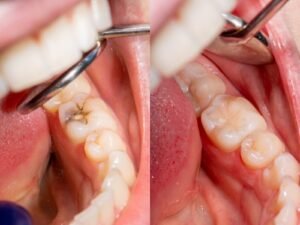

कैविटी बनने के बाद कोई भी घरेलू उपाय इसे ठीक नहीं कर सकता क्योंकि यह अंदर से सड़ी हुई और संक्रमित होती है। इसे केवल डेंटिस्ट की मदद से ही सही तरीके से साफ किया जा सकता है। डॉक्टर एक खास उपकरण से दांत के सड़े हुए हिस्से और उसमें मौजूद बैक्टीरिया को पूरी तरह साफ करते हैं। इसके बाद दांत में बने छोटे छेद को कंपोज़िट मटेरियल से भर दिया जाता है, जिसे फिलिंग कहते हैं। फिलिंग करवाने से दांत मजबूत हो जाता है, कैविटी बढ़ना रुक जाता है, दर्द बंद हो जाता है और दांत फिर से सड़ने से बच जाता है।